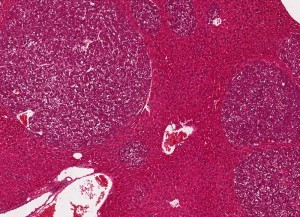

Leber einer kranken Maus, in der sich viele Tumore gebildet haben (Foto: Fabian Finkelmeier, kgu.de) |

Forscher der Goethe-Universität Frankfurt am Main, des Georg-Speyer-Hauses und des Universitätsklinikums Frankfurt sehen den sogenannten Eisentod (Ferroptose) als unterstützende Maßnahme einer Immuntherapie gegen Leberkrebs, mit dem der Körper kranke, defekte oder überflüssige Zellen abtötet. Experimente mit Mäusen im Labor hätten positive Ergebnisse geliefert.

Laut den Wissenschaftlern ist die neue Kombinationstherapie auch gegen Darmkrebsmetastasen in der Leber wirksam. Verabreichten die Experten erkrankten Mäusen eine Dreierkombination aus einem Ferroptose-Aktivator, einem Immun-Checkpoint-Blocker und einer Substanz, die verhindert, dass Myeloide Suppressorzellen angelockt werden, wurde das Wachstum der Lebertumore deutlich reduziert.

In weiteren Tests an Mäusen haben die Frankfurter Wissenschaftler zudem festgestellt, dass die Kombinationstherapie auch die Zahl der Lebermetastasen reduziert hat, die von einem streuenden Darmtumor stammten. Der Darmtumor selber sprach allerdings nicht auf die Kombinationstherapie an, heißt es.